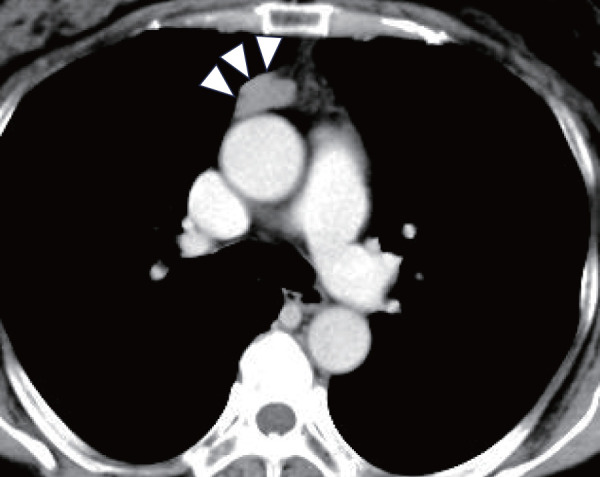

胸腺瘤通常与自身免疫性疾病相关,如重症肌无力(MG)、纯红细胞发育不全和低γ -球蛋白血症,而仅与斑秃(AA)相关的胸腺瘤极为罕见。一名55岁女性AA患者接受胸部计算机断层扫描,发现一个33毫米大小波动的前纵隔囊性肿块。她因疑似囊性胸腺瘤被转介到我科进行评估。患者在全麻下行胸腔镜肿瘤切除术,左侧卧位孤立肺通气。手术持续了81分钟,出血量最小,术后过程平稳。组织病理学证实为b2型胸腺瘤。值得注意的是,患者的AA在手术后迅速改善,至少3年内没有复发。该病例强烈提示AA和胸腺瘤之间存在潜在的免疫学关系,尽管需要进一步的研究来证实这种关系。

Thymomas are commonly associated with autoimmune diseases such as myasthenia gravis (MG), pure red cell aplasia, and hypogammaglobulinemia, while those associated solely with alopecia areata (AA) are extremely rare. A 55-year-old woman with AA underwent chest computed tomography, which revealed a 33-mm anterior mediastinal cystic mass with fluctuating size. She was referred to our department for evaluation of a suspected cystic thymoma. The patient underwent thoracoscopic tumor resection under general anesthesia with isolated lung ventilation in the left lateral decubitus position. The operation lasted 81 minutes with minimal blood loss, and her postoperative course was uneventful. Histopathology confirmed a type B2-dominant thymoma. Notably, the patient's AA improved rapidly after surgery and did not recur for at least 3 years. This case strongly suggests a potential immunological relationship between AA and thymoma, though further research is needed to confirm this relationship.